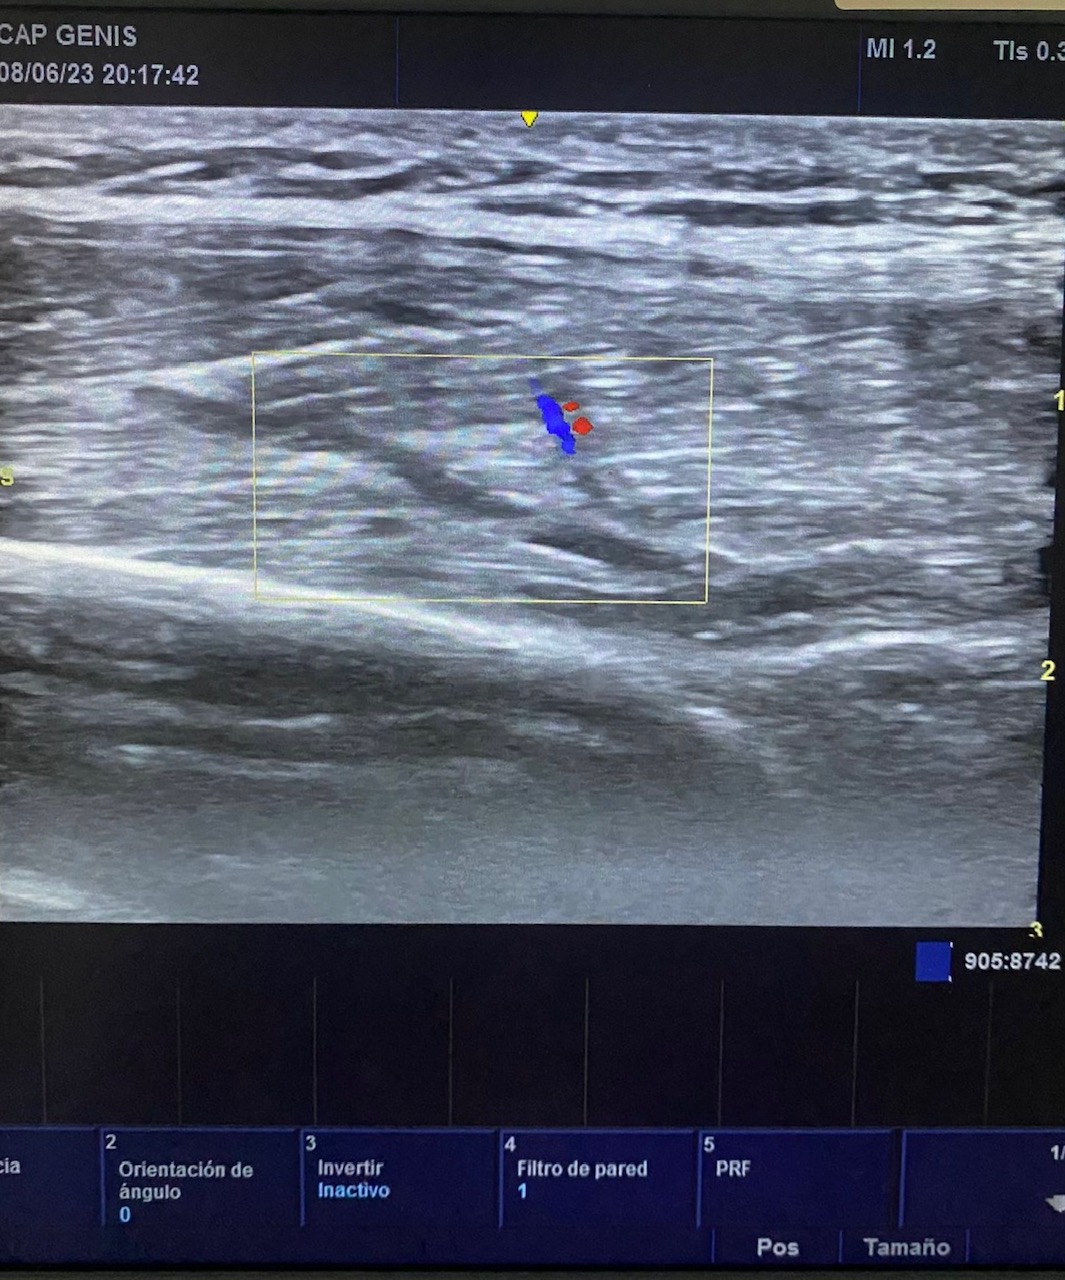

Hallazgos ecográficos

Se realiza ecografía a pie de camilla con transductor lineal sobre zona con dolor y se visualiza en corte longitudinal un defecto de la continuidad con zona hipoecogénica irregular en zona proximal de tríceps braquial izquierdo.

Por las características del mecanismo lesional, el cuadro clínico y la ecografía a pie de camilla se orienta como ruptura fibrilar de tríceps braquial izquierdo.